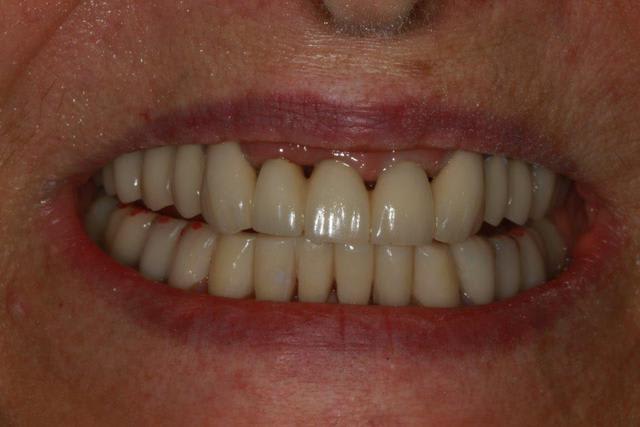

or si on regarde la photo de face ,elles sont de bonne proportion .elles sont bien intégrées .

ce qui confirme ,une fois de plus que ce sont les canines qui sont hyper dominantes et non pas les incisives qui sont trop petites .

là où on est embêté , ç est que ç était couru d'avance par le simple fait qu'il te manque la 22 ,et que donc l'arc du haut est trop resserré , du coup.

et puis tjs si on regarde de face ,même si les canines du bas sont en dysfonction par excès , elles ne sont pas vilaines non plus ,les hauteurs sont correctes ,et les bombés pas excessifs .

Smile beach jgh0a1 - Eugenol